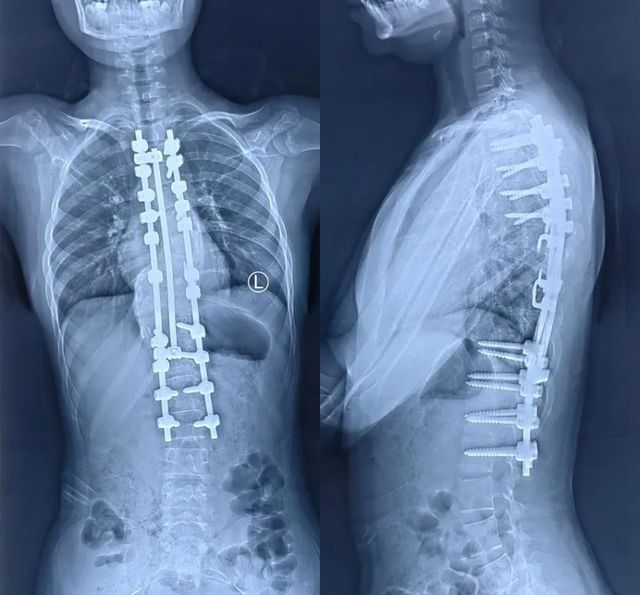

面对脆弱变形的脊柱结构,医疗团队制定四步矫形方案:先期采用halo-重力牵引渐进拉伸脊柱;术中借助天玑骨科机器人实现畸形椎体毫米级精准置钉;在神经电生理实时监护下完成高难度截骨松解;最终安装矫形棒对侧凸进行矫正,在顶椎区连接卫星棒予以加固。整个手术团队犹如在刀尖起舞,成功规避神经损伤风险。

通过多学科协作以及先进的医疗技术,包括机器人导航辅助手术、神经电生理监测等先进技术的应用,小莉的侧凸得到了良好的矫正,目前已经顺利出院。